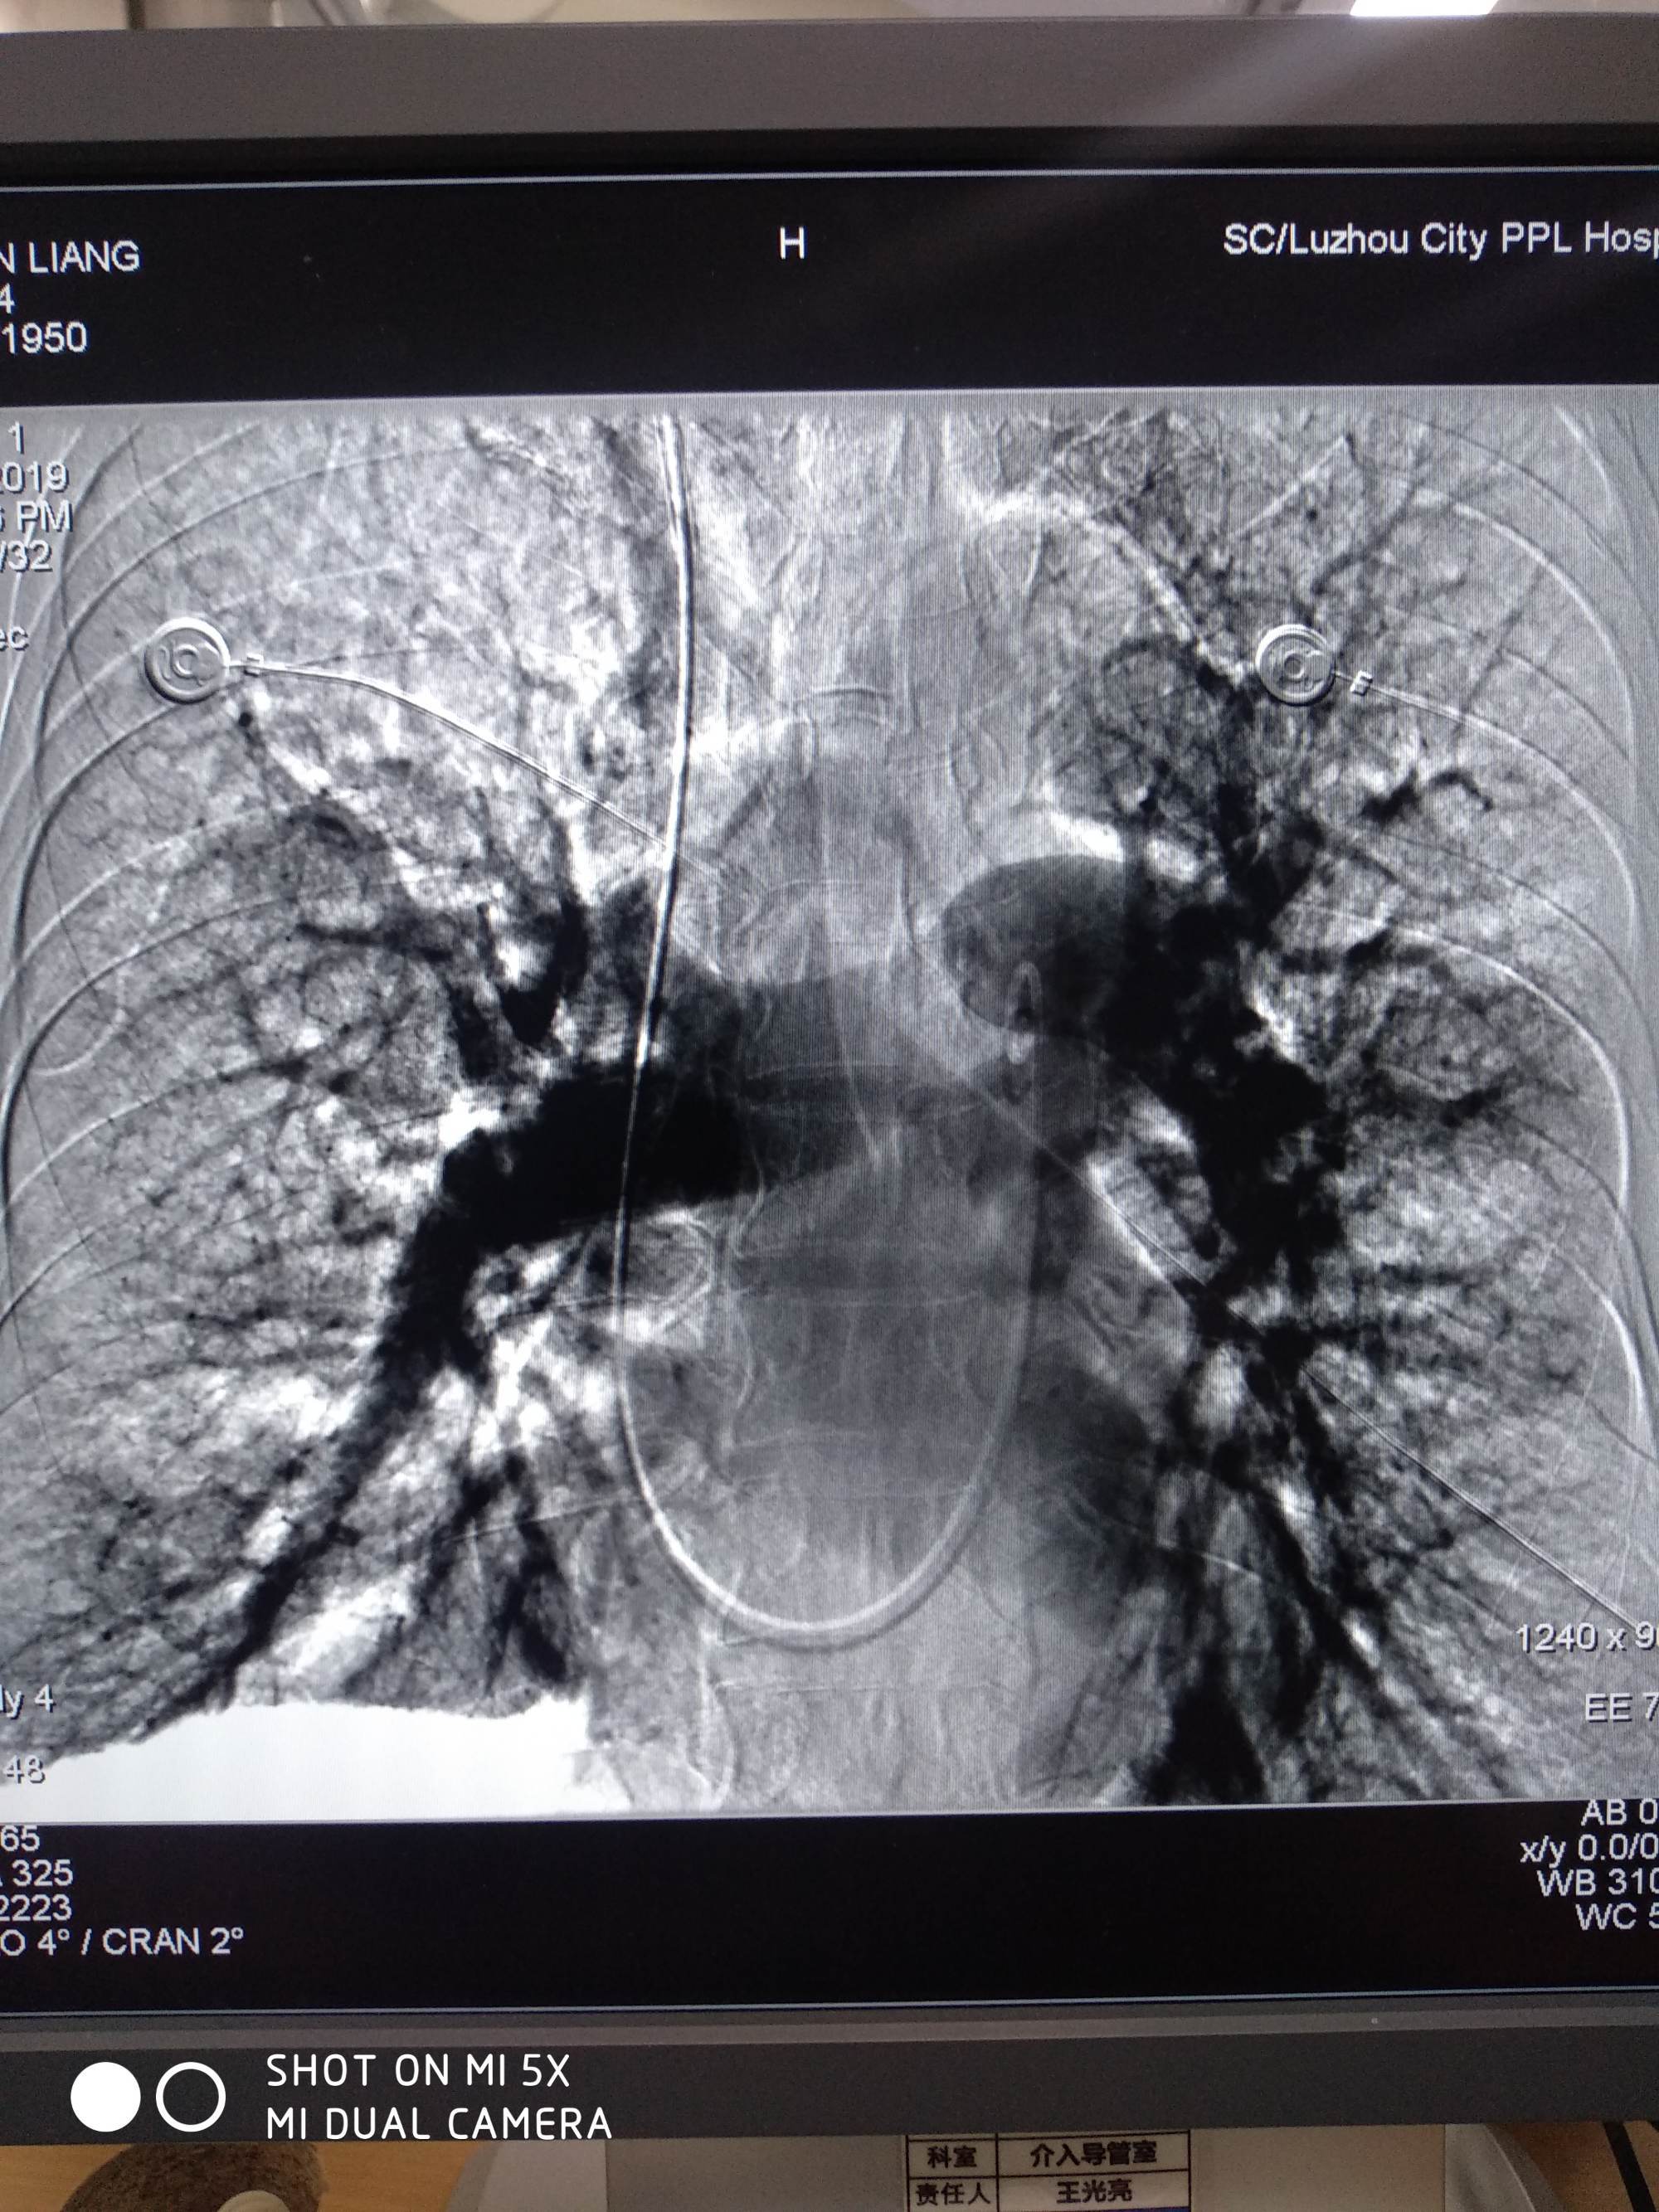

在这种患者内科治疗的效果是不理想的。因此,对于怀疑慢性肺栓塞引起肺动脉高压的患者应行肺动脉造影,肺扫描的灌注异常提供诊断的根据,解剖部位,肺动脉压力,选择适当的患者行血栓内膜切除术,能取得很好的结果。

这种手术的适应证包括严重呼吸功能不全、低氧血症、肺动脉高压、肺动脉造影肺栓塞在肺血管的近侧,支气管动脉造影有适当的栓塞远端的侧支循环,没有右心衰竭的患者。相反,患者是远侧肺动脉小分支的栓塞,严重右心功能衰竭和高度肥胖是手术禁忌证。当肺栓塞是在一侧,选择前外侧开胸,阻断肺动脉后,行血栓内膜切除术。当肺栓塞是在两侧或累及主肺动脉应采用正中开胸,体外循环。这种血栓是紧密地与血管壁粘连,行内膜剥脱术时应特别小心。所有的栓子均应取出,有时须在肺动脉的远侧再作切口,直到看到逆向血流。肺动脉切口的闭合最好用一条心包片,以防止狭窄。